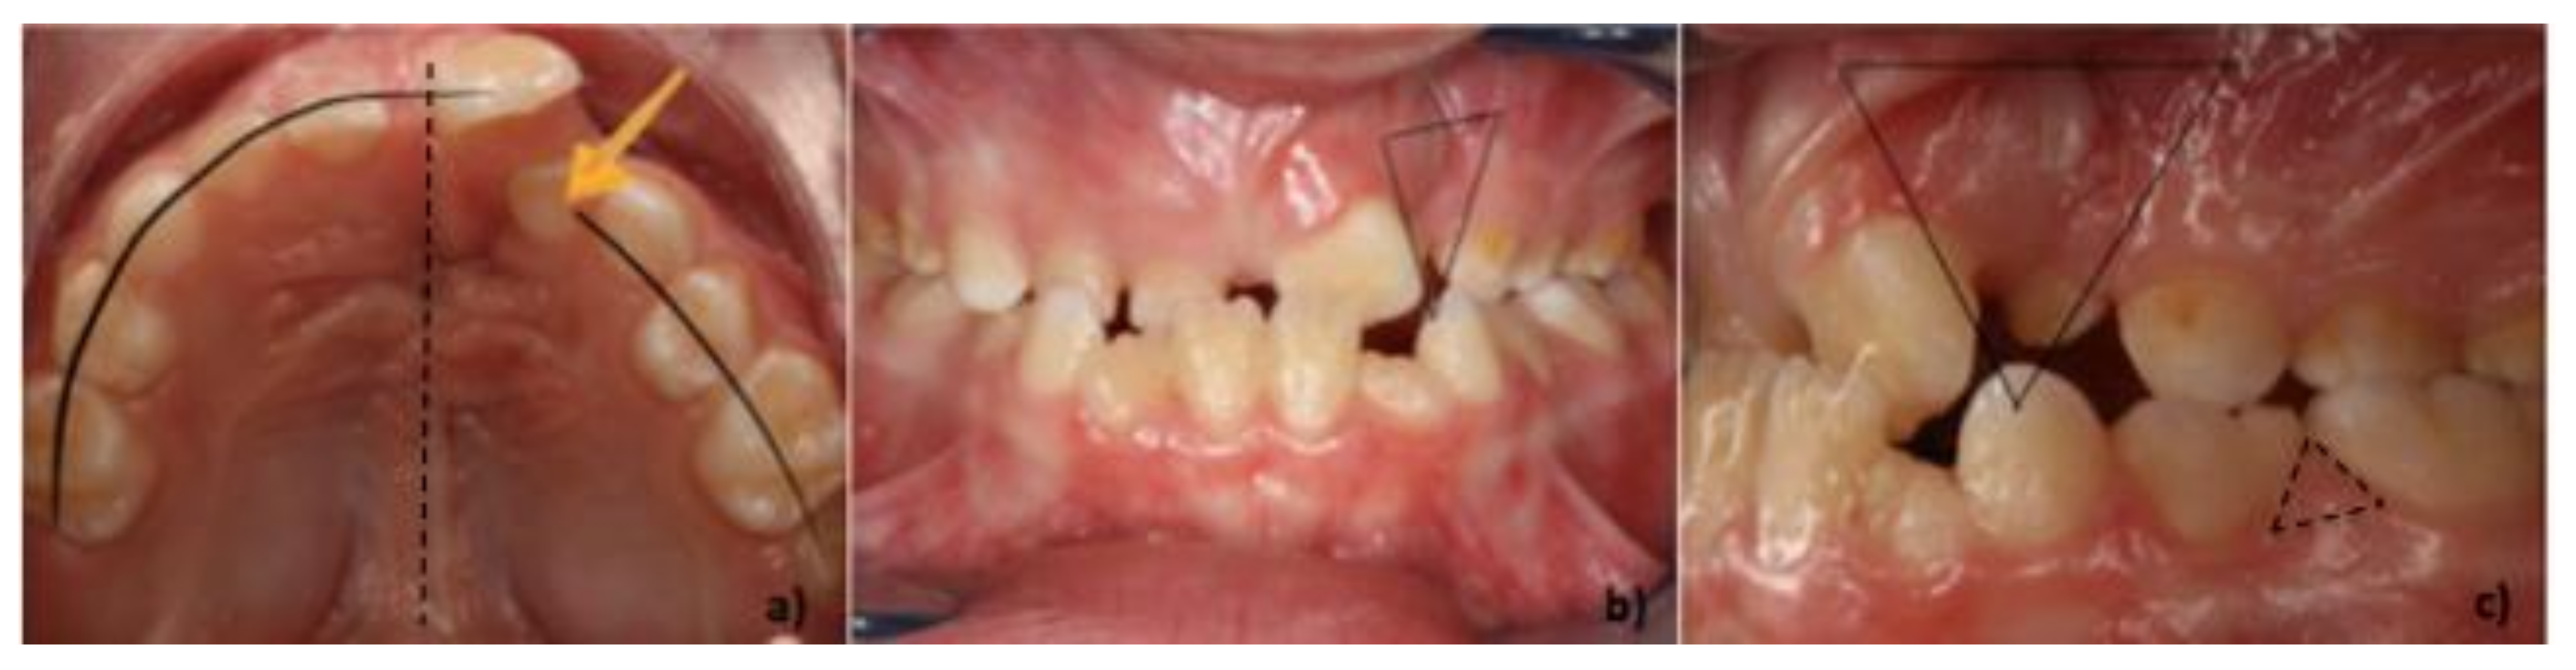

:1. Introduction

2. Design of the Cleft Toothbrush